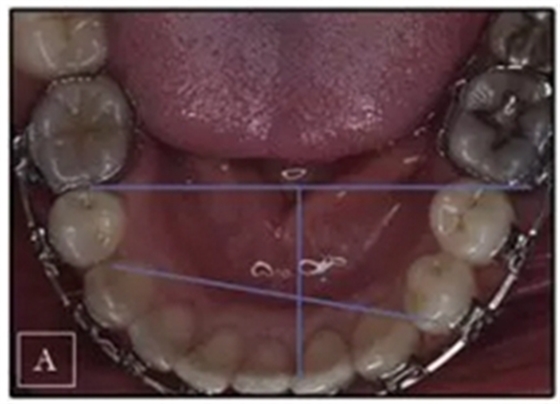

患者是一名39歲的白人婦女,病史不明。她主訴是她的右側(cè)顳下關(guān)節(jié)有不適癥狀,并希望改善她的笑容。她有一個(gè)對(duì)稱的臉型和一個(gè)II類2分類的微笑。她的側(cè)貌是凸的,90°的鼻唇角和骨性下頜骨發(fā)育不足??趦?nèi),上頜中線與面部重合,但下頜中線向右側(cè)偏移5mm;存在6mm的深覆蓋。她的兩側(cè)都是I類磨牙關(guān)系,左側(cè)是I類尖牙關(guān)系,右側(cè)是完全的II類尖牙關(guān)系。下頜右側(cè)第二前磨牙先天性缺失(圖1和圖2)。最初的全景片顯示了足夠的骨質(zhì)水平和全部的第三磨牙(圖3)。治療前的頭影測(cè)量片片和相應(yīng)的頭影測(cè)量圖(圖3)證實(shí)ANB為7°,Wits評(píng)估為6 mm的骨性II類錯(cuò)合(表)。上頜切牙相對(duì)與面部和顱底的位置很好。下頜切牙前傾。診斷為II類2分類錯(cuò)合畸形,伴有骨性下頜發(fā)育不足,右側(cè)顳下頜關(guān)節(jié)癥狀,下頜中線向右側(cè)偏移5mm,先天性右下第二前磨牙缺失。

圖1. 治療前照片

圖2. 治療前牙齒石膏模型